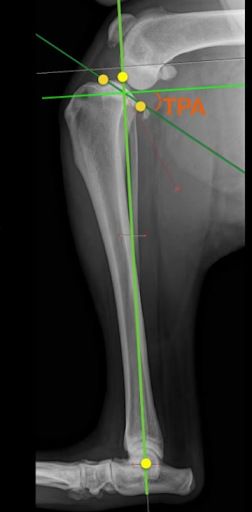

Following the identification of points of interests, and drawing of the lines of interest, i.e. the Functional Tibial Line (FTL) and the Medial Tibial Plateau Line (MTPL), another line is drawn such that the relation of new line and the FTL is 90°. Tibial plateau angle is the angle between this new line and the MTPL; this is shown in Fig. 3.

Normal TPA values can range from 18 to 25 degrees [1]; the large range can be attributed to the large range of breed, body weight, age etc.